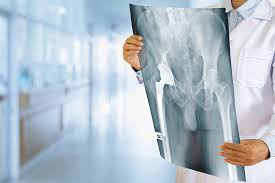

Proteza de șold totala pentru a.

Proteza de sold cand alte terapii de indepartare a durerii provocata de distrugerea soldului esueaza, inlocuirea articulatiei ar putea fi raspunsul. Peste 140 de pacienţi au beneficiat deja de o intervenție de protezare a genunchiului sau şoldului în cadrul spitalului repromed+. Procedura se va desfășura repetat, după eliberarea de către msmps rm a unei noi permisiuni.

Stiind ca am in istoric alergie la aur, am facut la synevo testul ltt. Înlocuirea articulaţiei şoldului se numeşte artroplastie. În timp ce osteoartrita poate afecta orice articulatie in corpul dumnavoastra mai ales la genunchiul si solduri.